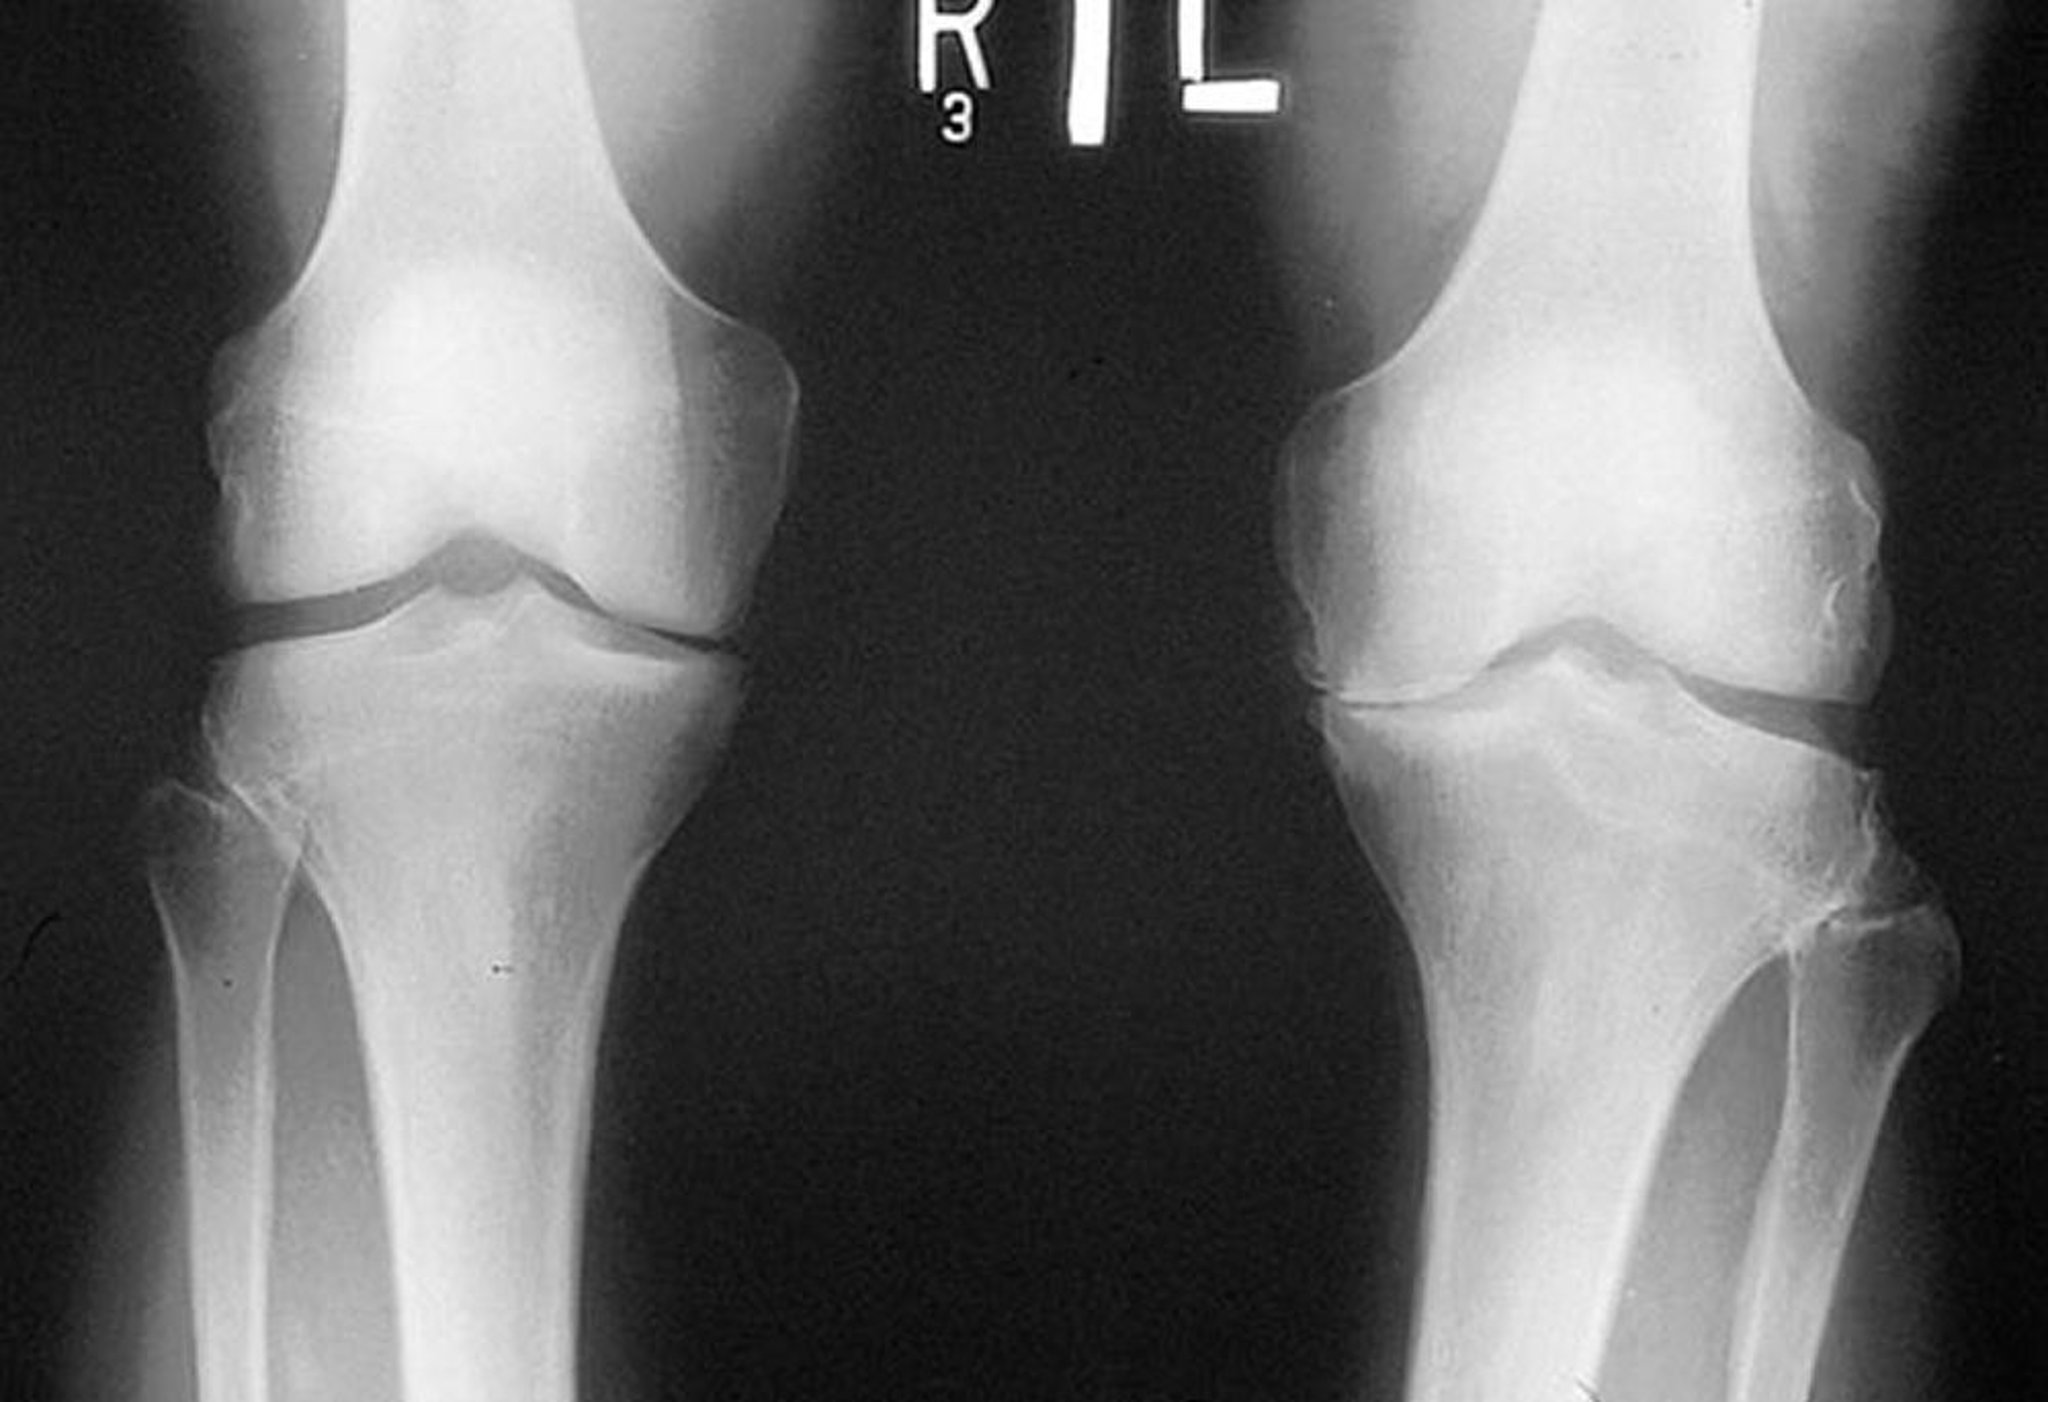

変形性関節症における膝関節のX線

このX線(患者が立位の状態で撮影)では,両膝関節(特に左側)の内側コンパートメントで大腿脛骨関節の関節裂隙が狭いことが示されている。辺縁に骨棘がみられる。左側の脛骨高原の内側に摩耗がある。